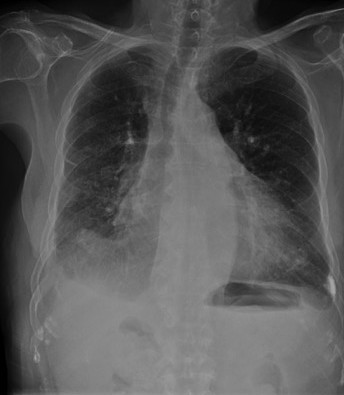

CASO: sospecha de neumonía.

Hallazgos:

- En un principio podríamos decir que existe un aumento de densidad retrocardiaco que podría ser compatible con condensación neumónica a dicho nivel, sin embargo estamos ante una placa poco inspirada, lo cual puede llevarnos a cometer errores diagnósticos.

- Se recomendó volver a realizar la radiografía, observar a continuación:

Ya no se observa el aumento de densidad retrocardiaco, la placa es normal.

INSPIRACIÓN: Una placa bien inspirada es aquella en la que se observar 6-7 arcos costales anteriores o 10-11 arcos costales posteriores. Lo contrario puede producir imágenes falsas de condensaciones o de seudocardiomegalia.